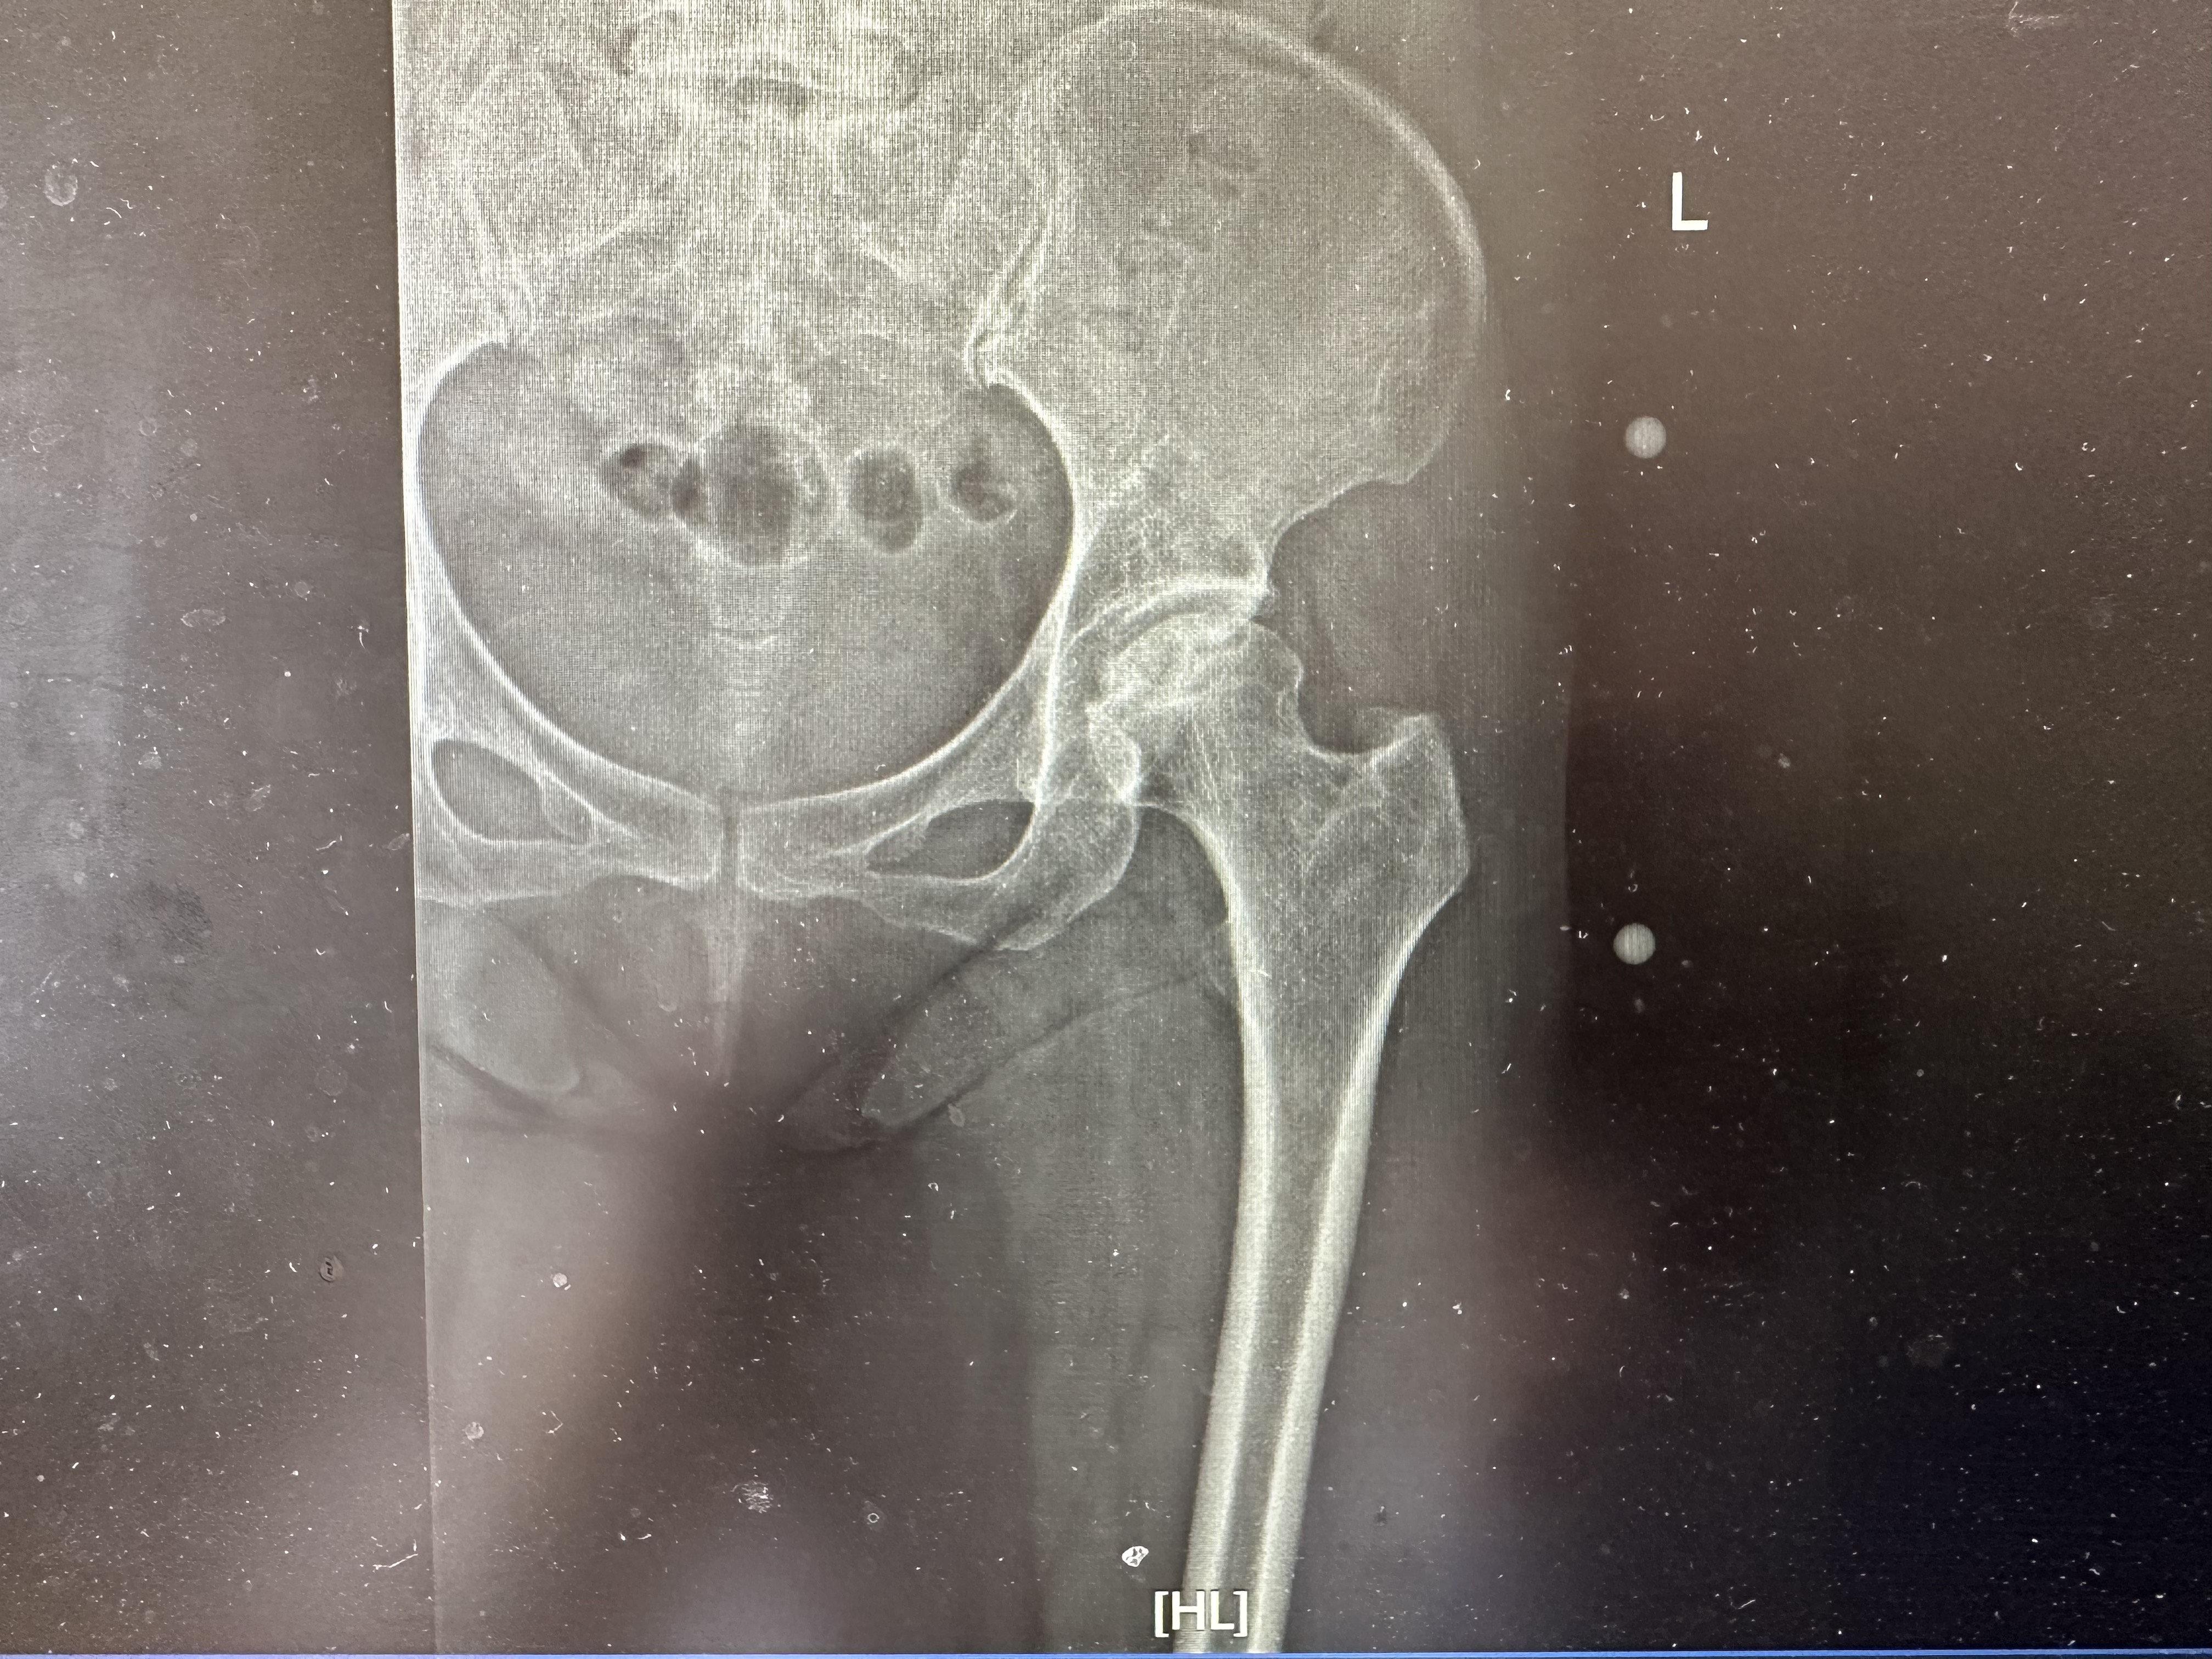

?4.ARCO分期(國(guó)際骨循環(huán)研究會(huì)分期-目前最推薦的標(biāo)準(zhǔn))???目標(biāo):整合之前各分期系統(tǒng)的優(yōu)點(diǎn),建立一個(gè)國(guó)際通用的標(biāo)準(zhǔn)。???基礎(chǔ):結(jié)合影像學(xué)(X線、CT、骨掃描、MRI)、臨床癥狀和功能檢查。???最新版(ARCO2019):????分期(Stage0-IV):類似于Ficat和Steinberg,但定義更清晰。??????0期:風(fēng)險(xiǎn)因素存在,所有檢查正常,組織學(xué)證實(shí)壞死。??????1期:影像學(xué)(X/CT正常),MRI或骨掃描陽(yáng)性。無(wú)癥狀或有癥狀。??????2期:X/CT見(jiàn)骨質(zhì)改變(硬化、囊變、骨質(zhì)疏松),無(wú)塌陷(新月征陰性)。MRI/骨掃描陽(yáng)性。??????3期:出現(xiàn)新月征(軟骨下骨折)和/或股骨頭塌陷(扁平)。關(guān)節(jié)間隙正常。分亞型:???????3A:早期塌陷(新月征長(zhǎng)度<15%關(guān)節(jié)面或塌陷深度<2mm)???????3B:中期塌陷(新月征長(zhǎng)度15%-30%或塌陷深度2-4mm)???????3C:晚期塌陷(新月征長(zhǎng)度>30%或塌陷深度>4mm)??????4期:關(guān)節(jié)間隙變窄,髖臼出現(xiàn)骨關(guān)節(jié)炎改變(硬化、囊變、骨贅)。